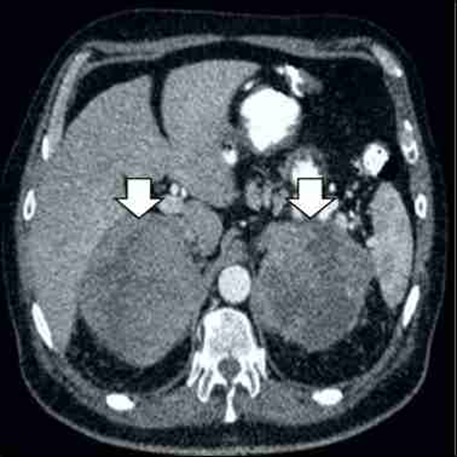

La ecografía abdominal demostró tumores en ambas glándulas suprarrenales. Este hallazgo fue confirmado por imágenes de la tomografía computada que identificaron tumoraciones grandes, heterogéneas y necróticas en ambas glándulas suprarrenales con contornos lobulados (11 x 8 x 7 centímetros de diámetro para la glándula suprarrenal derecha y 9 x 6 x 5 centímetros de diámetro para la glándula suprarrenal izquierda), sin evidencia de linfadenopatías retroperitoneales o afección visceral (figura 1). Las imágenes de tomografía computarizada del resto del cuerpo fueron negativas para cualquier linfadenopatías o compromiso de otros órganos. La tomografía por emisión de positrones mostró captación intensa de fluorodesoxiglucosa en ambas glándulas suprarrenales sin captación por los ganglios linfáticos paraaórticos retroperitoneales (figura 2). La radiografía de tórax, la endoscopia superior y la colonoscopia no mostraron hallazgos anormales.